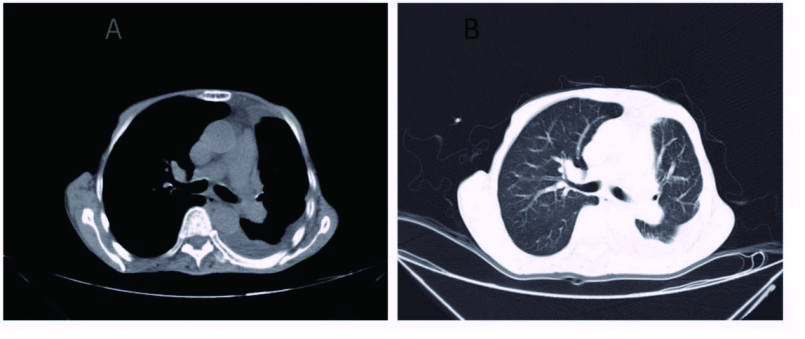

1 资料与方法患者男,70岁,农民,入院前3 d受凉后出现咳嗽,为阵发性干咳、无痰,伴胸闷、气喘,平卧及活动时加重,发热,体温最高37.7 ℃,热型未监测,无畏冷、寒战;当地医院胸部X线平片示左侧胸腔积液、左侧肺炎,予以“头孢噻肟”抗感染治疗无效,于2015年9月29日转来厦门大学附属第一医院。既往慢性支气管炎病史20余年,吸烟史50年×40支/d。入院时查体:T 37.6 ℃,P 106次/min,R 26次/min,BP 118/72 mmHg,SPO2 91%,神志清楚,反应迟钝,有时答非所问,呼吸较急促,气管轻度右偏;左侧胸部呼吸运动减弱,语颤消失,叩诊呈浊音,呼吸音减弱,右肺散在哮鸣音;心界不清,心率106次/min,节律规整,各瓣膜区未闻及杂音。入院后观察患者热型为不规则低热,查血尿粪常规、肝肾功能、肿瘤标志物等正常,降钙素原0.826 ng/mL,结核抗体及结核菌素实验阴性。血气分析:氧分压6.63 kPa,二氧化碳分压正常,无酸碱失衡表现。胸部CT示,双肺多发感染,左侧大量胸腔积液;右肺局限性肺大泡,肺气肿(图 1)。入院后给予莫西沙星抗感染,胸腔穿刺引流出大量淡红色稍混浊胸水,无臭味,每日引流量300~600 mL;胸水常规:李凡他试验阳性,蛋白48.6 g/L,有核细胞数1 520×106/L,比重1.021。患者仍有反复低热,热峰及持续时间稍改善。入院后10 d胸水培养结果回报为星型奴卡菌感染(图 3、4),抗生素更换为TMP-SMX 0.96 g/12 h联合红霉素0.25 g/8 h治疗,体温逐渐下降至正常,咳嗽、气喘症状缓解,胸水引流量逐渐减少至消失,PCT和血气分析结果恢复正常,胸部CT:左侧少量胸腔积液,伴积气(图 2)。于2015年10月25日出院,继续口服TMP-SMX片及红霉素片治疗,定期随诊。患者感觉恢复良好在出院后1个月左右自行停药,3个月后因右侧肢体无力再诊我院,颅脑MRI提示:大面积小脑梗死,脑疝并幕上脑积水(图 5),再诊时未再复查胸部CT,2 d后因呼吸循环衰竭死亡,家属未同意尸检。

| 图 2 胸腔穿刺术后,可见左肺复张,双肺纹理清晰,伴少量积气(A:纵隔窗; B:肺窗) |